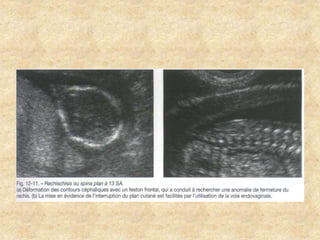

Aspect du rachis

Malformations fœtales d’expression précoce Pathologiedes parties molles Pathologie du système nerveux central Pathologie des parois Pathologie urinaire Pathologie des membres Pathologie cardiaque